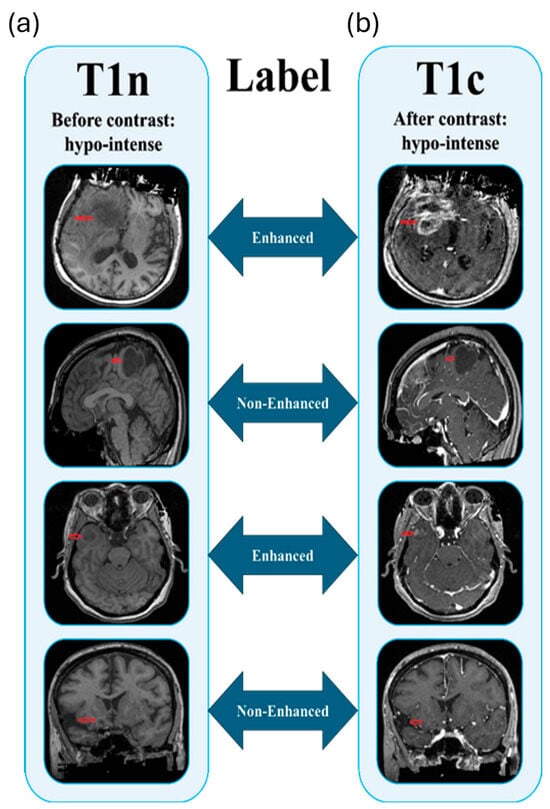

Enhancement Without Contrast: Stability-Aware Multicenter Machine Learning for Glioma MRI Imaging

Gadolinium-based contrast agents (GBCAs) are vital for glioma imaging yet pose safety, cost, and accessibility issues; predicting contrast enhancement from non-contrast MRI via machine learning (ML) provides a safer, economical alternative, as enhancement indicates tumor aggressiveness and informs treatment planning. However, scanner and [...] Read more.

Gadolinium-based contrast agents (GBCAs) are vital for glioma imaging yet pose safety, cost, and accessibility issues; predicting contrast enhancement from non-contrast MRI via machine learning (ML) provides a safer, economical alternative, as enhancement indicates tumor aggressiveness and informs treatment planning. However, scanner and population variability hinder robust model selection. To overcome this, a stability-aware framework was developed to identify reproducible ML pipelines for predicting glioma contrast enhancement across multicenter cohorts. A total of 1367 glioma cases from four TCIA datasets (UCSF-PDGM, UPENN-GB, BRATS-Africa, BRATS-TCGA-LGG) were analyzed, using non-contrast T1-weighted images as input and deriving enhancement status from paired post-contrast T1-weighted images; 108 IBSI-standardized radiomics features were extracted via PyRadiomics 3.1, then systematically combined with 48 dimensionality reduction algorithms and 25 classifiers into 1200 pipelines, evaluated through rotational validation (training on three datasets, external testing on the fourth, repeated across rotations) incorporating five-fold cross-validation and a composite score penalizing instability via standard deviation. Cross-validation accuracies spanned 0.91–0.96, with external testing yielding 0.87 (UCSF-PDGM), 0.98 (UPENN-GB), and 0.95 (BRATS-Africa), averaging ~0.93; F1, precision, and recall remained stable (0.87–0.96), while ROC-AUC varied (0.50–0.82) due to cohort heterogeneity, with the MI + ETr pipeline ranking highest for balanced accuracy and stability. This framework enables reliable, generalizable prediction of contrast enhancement from non-contrast glioma MRI, minimizing GBCA dependence and offering a scalable template for reproducible ML in neuro-oncology. Full article

(This article belongs to the Special Issue Machine Learning Applications in Healthcare and Disease Prediction)

Show Figures

Figure 1